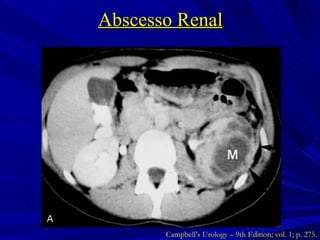

Abscesso Renal Coleção de material purulento confinado ao parênquima renal Inoculação hematogênica Gram + ( Staphylococci ) Formação no córtex renal  Infecção ascendente Gram – ( E. coli ) Formação na junção córtico-medular Campbell’s Urology – 9th Edition; vol. 1; p. 273 e 274.

Abscesso Renal Campbell’s Urology – 9th Edition; vol. 1; p. 275.

Abscesso Renal Tratamento  Abscessos < 3 cm ATB de amplo espectro direcionado à etiologia  Abscessos > 3 cm, imunodeprimidos ou falha do tratamento clínico Drenagem percutânea Campbell’s Urology – 9th Edition; vol. 1; p. 275 e 276.